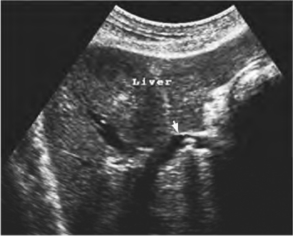

2.肝内胆管结石(图25-13) 肝内与门静脉分支相伴行部位见到团状强回声,其周围有宽窄不等的无回声区,后伴声影,可见其远端肝内胆管扩张。

图25-13 肝内胆管结石(箭头所示)声像图